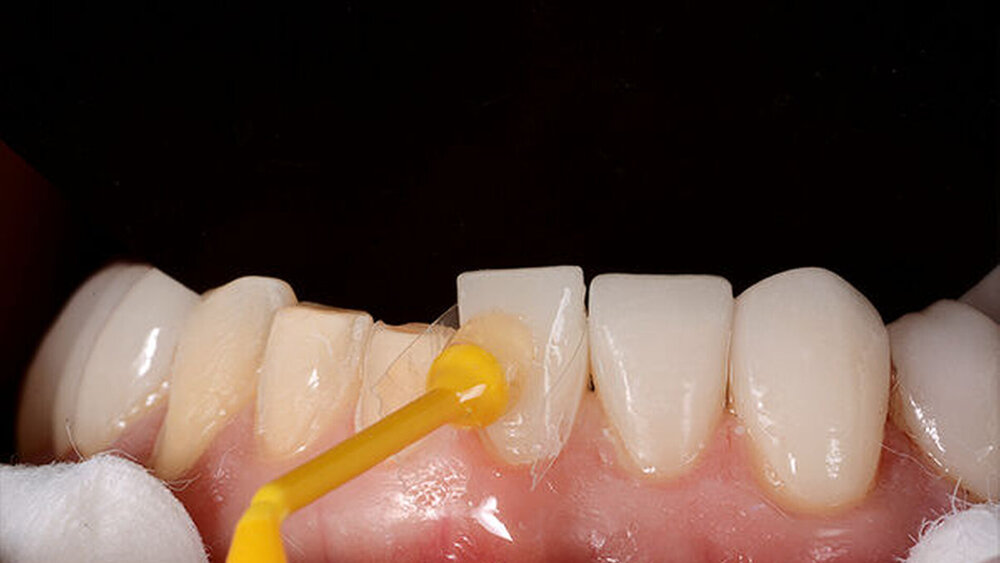

Die endgültigen Veneers und Kronen wurden mit der Konstruktionssoftware „Ceramill mind“ (Amann Girrbach) digital vorbereitet und in einer Fräsmaschine (Ceramill Motion 2, Amann Girrbach) aus maschinell bearbeitbaren Lithiumdisilikat-Keramikblöcken (VITA BLOCS TriLuxe forte für Ceramill Motion 2, Amann Girrbach) gefertigt (Abb. 10). Nach der Bestätigung des Randschlusses und der optischen Eigenschaften bei einem probeweisen Einsetzen wurde ein Lippen-Wangen-Halter (OptraGate, Ivoclar Vivadent) angelegt.

Die Pfeilerzähne und Keramikveneers und -kronen wurden gemäß den Herstellerempfehlungen präpariert: Die Keramikoberfläche wurde mit Aluminiumoxid 50 µm und 20 s mit Flusssäure 5 % präpariert, dann 20 s gespült, danach mit Phosphorsäure 37 % (Total Etch, Ivoclar Vivadent) und Alkohol 96 % zur Reinigung behandelt und ausschließlich 20 Sekunden mit Silan konditioniert (Monobond Plus, Ivoclar Vivadent).

Die Kronen (11–13, 21–23) und Veneers (14, 15, 16, 17, 24, 25, 26, 27, 31, 32, 33, 34, 35, 36, 37, 41, 42, 43, 44, 45, 46, 47) wurden mit einem lichthärtenden, polymerisierenden Harz‧adhäsiv (Futurabond U und Bifix QM; VOCO) an den Abutments befestigt. Zur Polymerisation wurde ein Hochleistungs-LED-Lichthärtegerät verwendet (Celalux 3; VOCO), siehe die Abbildungen 11 und 12.